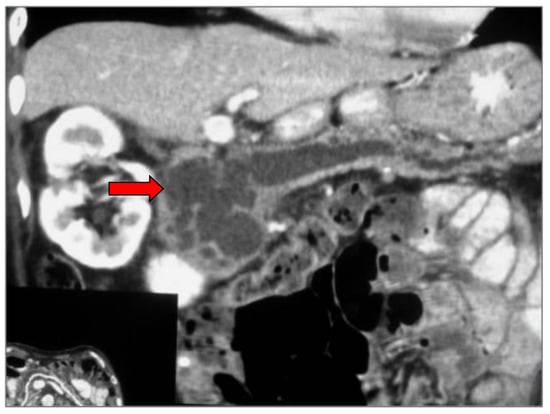

2. Imaging Findings